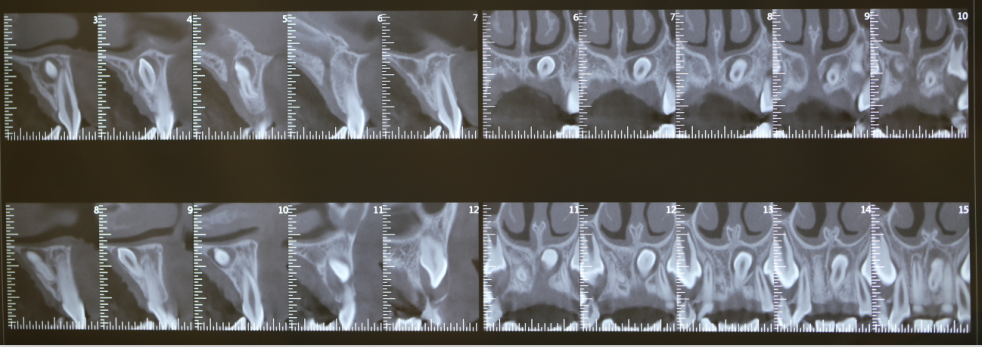

牙如果有条件可以拍摄CBCT,在不同的轴向观察多生牙与邻牙的位置,还可以判断距唇腭侧骨表面的距离及与组织之间的关系,更加利于术中操作。